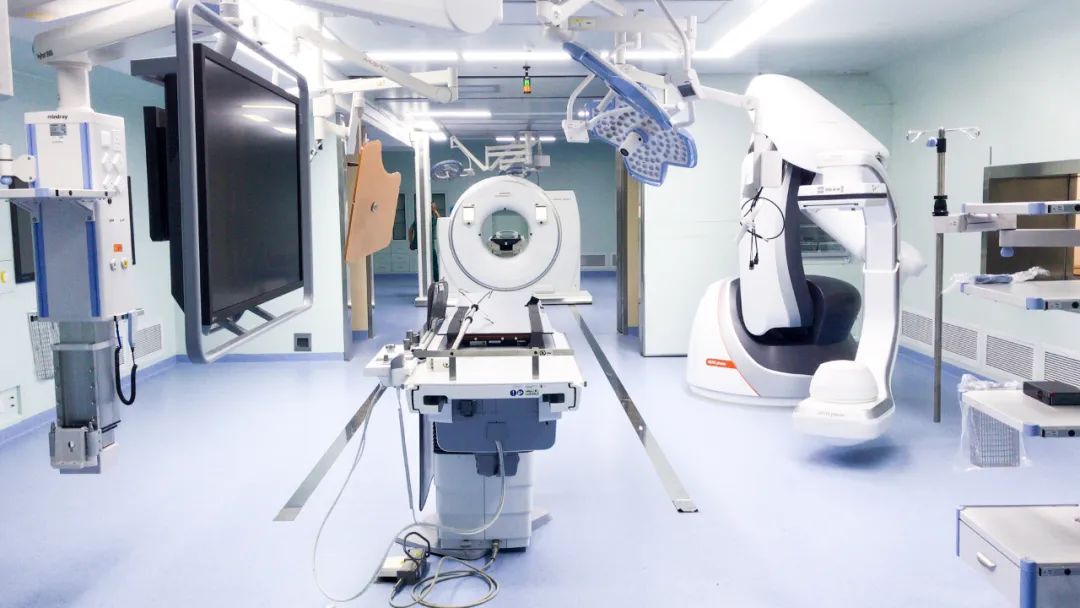

我院肝癌多学科诊疗MDT团队,在国内西南地区具有较强的业务综合实力,肝癌规范诊疗质量控制中心治疗体系完善,技术实力在广西处于领先水平,占据较高的学术地位。分专业开设肿瘤化疗科,肝脏外科,肿瘤放疗科、微创介入治疗及生物免疫治疗等多个亚专业病区,执行一体化管理及MDT多学科诊疗模式。团队高级职称、博士医疗专家团队29人,可开展50余项高难度治疗技术,其中达芬奇辅助外科手术、腹腔镜下肝切术、立体定向放疗、影像调强放疗、容积调强放疗、步进式调强放疗、CT引导肝肿瘤冷热消融技术等均处于国内先进水平;中心配备国内外顶尖仪器设备包括:广西首台第四代螺旋断层放射治疗系统(TOMO)、320排超能螺旋CT机、西门子飞龙3D CT-DSA杂交手术室;广西桂中地区第一台达芬奇XI机器人、PET-CT等众多超高端大型医疗装备。

“飞龙”杂交手术室